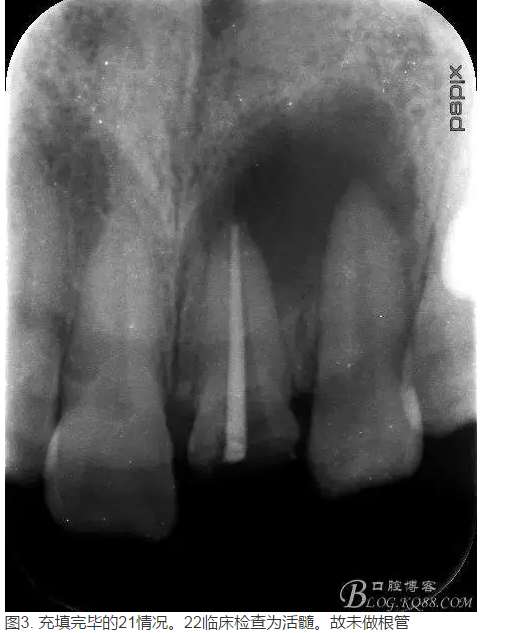

轉:張東星 愛齒-KQ88口腔醫(yī)學